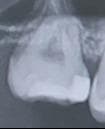

27번 치아입니다 약 2~3년전 인레이를 받았었는데 아무런 증상이 없지만 치실사용시 뭔가 걸리는 느낌은 있습니다.

그래서 사진을 둘러보다 인레이 한 주위부위가 들뜬건지 아니면 충치가 생긴건지, 또는 그냥 약재에 의한 약간의 회색인지 잘 모르겠어서 한번 보시고 판단해 주시면 감사하겠습니다.

사진으로만 봤을 경우에는 충치가 있는것으로 보이지는 않습니다 하지만 육안으로도 확인이 필요할것으로 생각됩니다.

엑스레이 상으로는 크게 문제가 없어 보입니다. 주변부에 접착제때문에 사진처럼 보일수도 있습니다.

그다지 문제가 될 것으로 보이지는 않습니다. 내부에 비쳐보이는 부분도 있어 화질이 더 좋으면 도움이 됩니다.